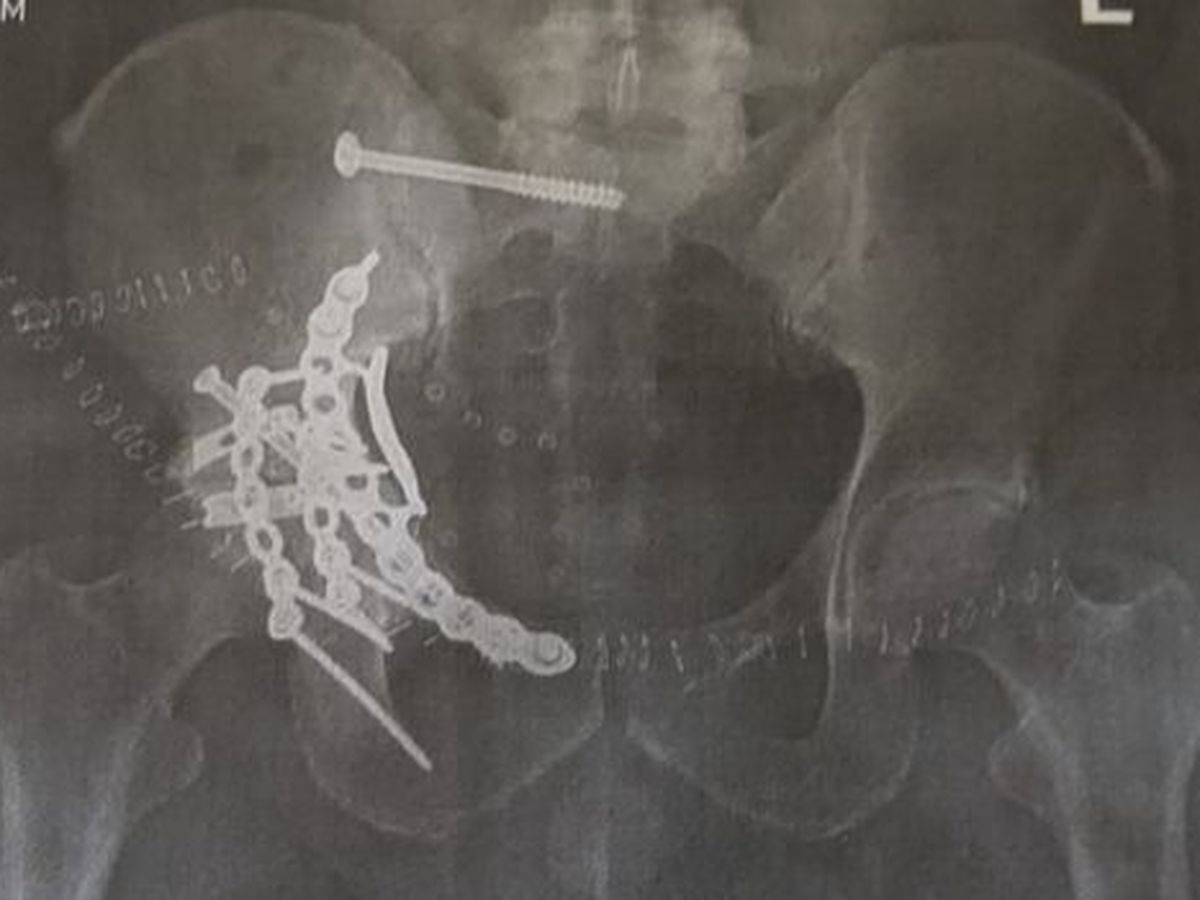

On September 9th, 2020 – my brother Joey was in an ATV Accident. He was thrown from the vehicle and landed on his hip. He has a very long road ahead of him. After 2 weeks in the hospital and 2 surgeries, he is home healing from his ordeal. Joey had a 6-hour surgery on 9/14/20 to address his shattered acetabular. Then a 2nd long surgery on 9/18/20 to repair his pelvic ring, and reposition his pelvis that was shifted back and up towards his navel, and damage to his lower 3 vertebrae in his back.